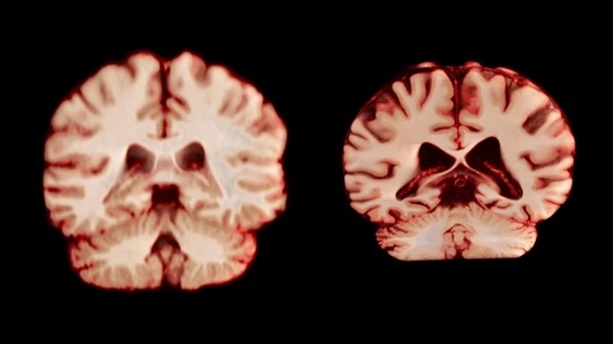

Болезнь Альцгеймера — наиболее распространенная форма деменции, при которой постепенно разрушаются клетки мозга, что приводит к потере памяти и когнитивных функций. Старение является главным фактором риска этого заболевания. Женщины составляют почти две трети всех пациентов с болезнью Альцгеймера, и долгое время ученые предполагали, что это связано с более быстрым старением женского мозга или большей продолжительностью жизни женщин. Новое исследование опровергает гипотезу о скорости возрастных изменений мозга как причине этого дисбаланса.

Исследование, опубликованное в журнале Proceedings of the National Academy of Sciences, включило данные 4726 человек без когнитивных нарушений из 14 крупных баз данных. Каждый участник прошел минимум два МРТ-обследования с интервалом в среднем три года. Ученые сравнивали, как менялись структуры мозга со временем, включая толщину серого вещества и размер областей, связанных с болезнью Альцгеймера, таких как гиппокамп.

Соавтор исследования Анне Равндаль объясняет: «Если бы мозг женщин деградировал сильнее, это могло бы объяснить более высокую распространенность среди них болезни Альцгеймера». Но данные показывают обратное. Если бы возрастные изменения играли роль в развитии болезни Альцгеймера, женщины демонстрировали бы более значительное уменьшение в связанных с заболеванием областях, таких как гиппокамп и предклинье, отвечающие за память.